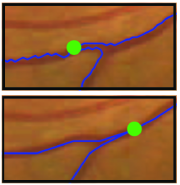

Appearance is one of the most important visual cues to distinguish between different structures in an image. Appearance is described by studying the distribution of different features such as intensity values in gray-scale images, color, and texture inside each object. In most cases, appearance models are incorporated into the data term in (2) and (7). The purpose of incorporating appearance prior is to fit the appearance distribution of the segmented objects to the distribution of objects of interest, e.g. using Gaussian mixture model (GMM) (Rother et al., 2004). In the literature, there are two ways to model the appearance: 1) adaptively learning the appearance during the segmentation procedure, and 2) knowing the appearance model prior to performing segmentation (e.g. by observing the appearance distribution of the training data). In the former case, the appearance model is learned as the segmentation is performed (Vese and Chan, 2002) (computed online). In the second case, it is assumed that the probability of each pixel belonging to particular label is known, i.e. if represents a particular set of feature values (e.g. intensity/color) associated with each image location for object, then it is assumed that is known (or pre-computed offline). This probability is usually learned and estimated from the distribution of features inside small samples of each object. Figure 9 illustrates the probability of different structures (the kidney, the tumour, and the background) in an endoscopic scene. A lower intensity in Figures 9(b-d) corresponds to higher probability.